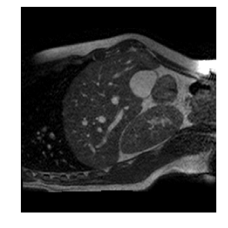

With this motivation, [6] proposed a convolutional neural network (CNN) based approach for temporal interpolation of navigators. Their CNN takes as inputs a fixed number of acquired images and learns to predict the missing images directly in the intensity space. This approach, which we call the Simple Convolutional Interpolation Network (SCIN), is a ’black-box’ formulation that does not incorporate any prior information about the interpolation process. Image prediction is guided only by the cost function used to optimize the network parameters. The issue with this is that it is unclear whether the image similarity measures that are generally used as cost functions suffice to ensure fidelity of the generated images to the original images. Indeed, Fig. 1b shows a case where an image interpolated using SCIN is quite blurry and misses several liver and lung structures present in the original image.

(a)                                (b)                                (c)

Figure 1: (a) Ground truth and (b,c) interpolated images from (b) baseline (SCIN) and (c) proposed method (MFIN). The image interpolated via SCIN is heavily blurred and misses several lung and liver structures, while the proposed method is able to preserve the details in the ground truth image.